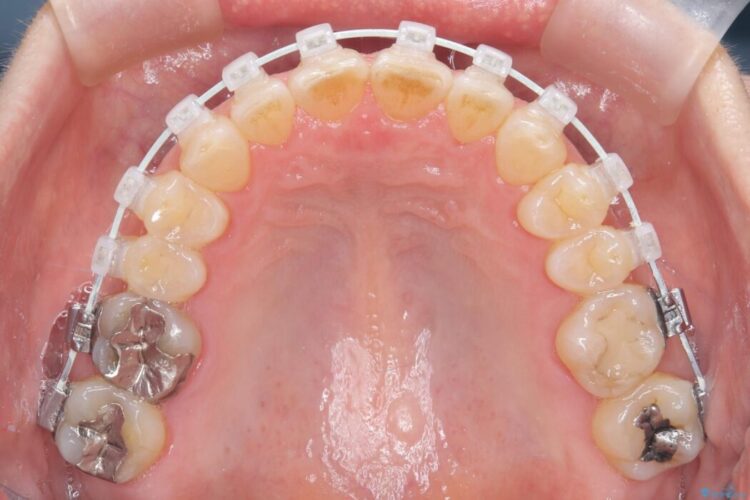

- 矯正装置:審美装置

今回の矯正治療では、歯の色に近い目立たない審美ブラケットとワイヤーを使用しました。

ワイヤー矯正ならではの確実な歯のコントロールにより、当初の計画通り約1年という短い期間で、前歯のガタつきが解消。見た目が美しく整っただけでなく、清掃しやすい機能的な歯並びを獲得していただけました。